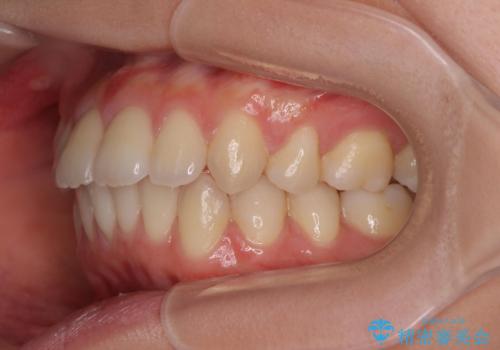

突き出た前歯の改善!マウスピースで再矯正

- 5年前にワイヤー矯正治療を終了したが、突き出たように見える前歯の仕上がりが気に入らず、再矯正治療を希望され来院されました。

マイクロインプラントを用いた遠心移動とIPRを行うことによる前歯の突出感の改善をマウスピース矯正治療で計画します。

突出していた前歯の角度が大きく改善し、審美的な仕上がりに満足いただくことができました。